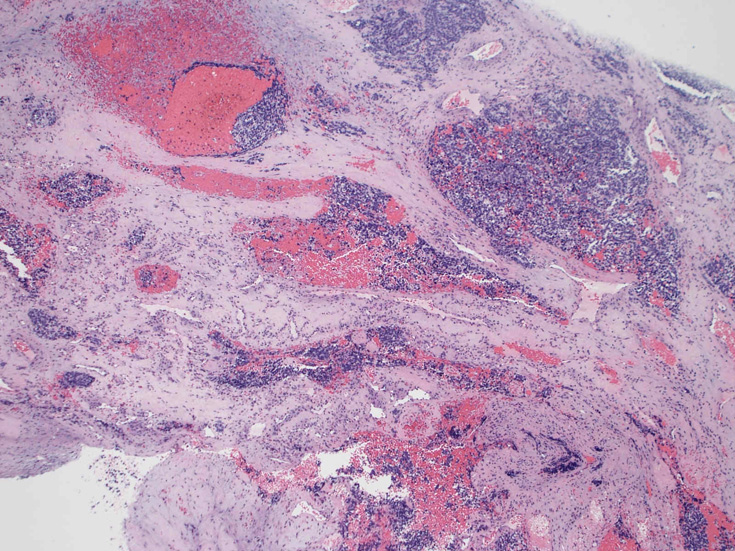

症例--鼻腔腫瘤

30歳代男性 鼻腔腫瘤の生検組織

厳密にはalveolar patternが明らかではなく, solid typeに入る症例かもしれない。異型細胞増殖胞巣が線維化組織に取り囲まれるように散在している. 小さな生検組織のため全体像が不明である。

鼻腔腫瘤生検組織